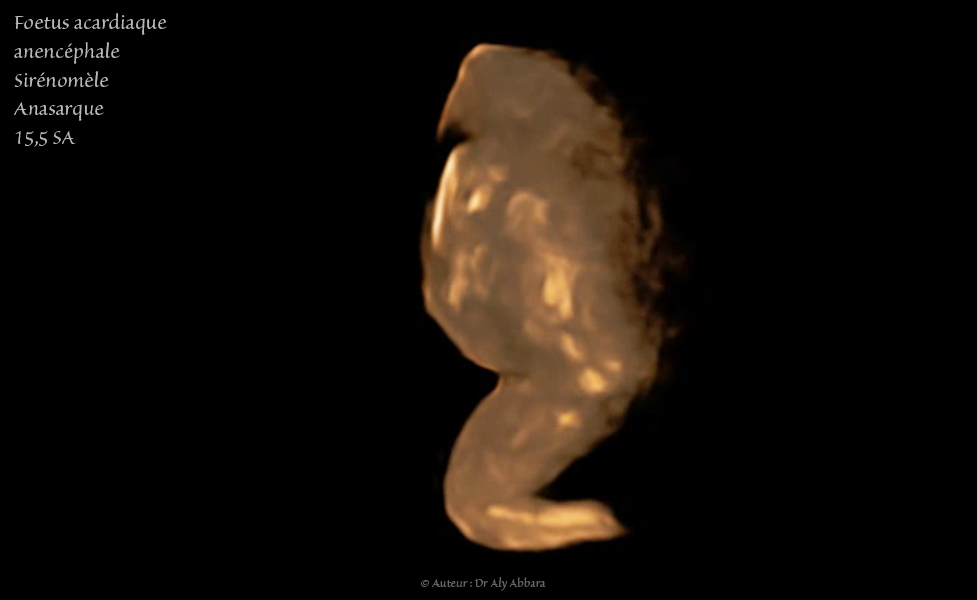

Grossesse gémellaire monochoriale bi-amniotique à 15,5 SA avec un jumeau polymalformé :

Anencéphalie, amélie bilatérale supérieure, sirénomélie, oedème généralisé - Rotation axiale, couleur sépia

• Foetus acardiaque : pas structures cardiaques (holoacardius), mais la présence d'une vascularisation provenant de l'autre jumeau normal (jumeau pompe) par le cordon ombilical.

Anencéphale (acrânie - acranius) : absence de structures céphaliques identifiables.

• Amélie des membres supérieurs (absence des deux extrémités supérieures)

• Sirénomélie : un seul membre inférieur comportant deux segments : supérieur avec un fémur, et inférieur contenant deux os longs, mais apodie (absence de pied). Ce membre inférieur est parfois animé par certains mouvements de type flexion - déflexion très réduites.

• Probable vessie (entourée par les deux artères ombilicales) ; une structure digestive liquidienne ; un segment désorganisé du rachis ; quelques côtes incomplètes.

• Un œdème fœtale généralisé sous-cutané majeur enveloppant ce fœtus acardiaque.

• L'estimation du poids de ce jumeau acardiaque est égale 7,7 grammes pour une longueur de 3,3 cm, contre 118 grammes + 10 % pour le jumeau pompe (donneur normal).